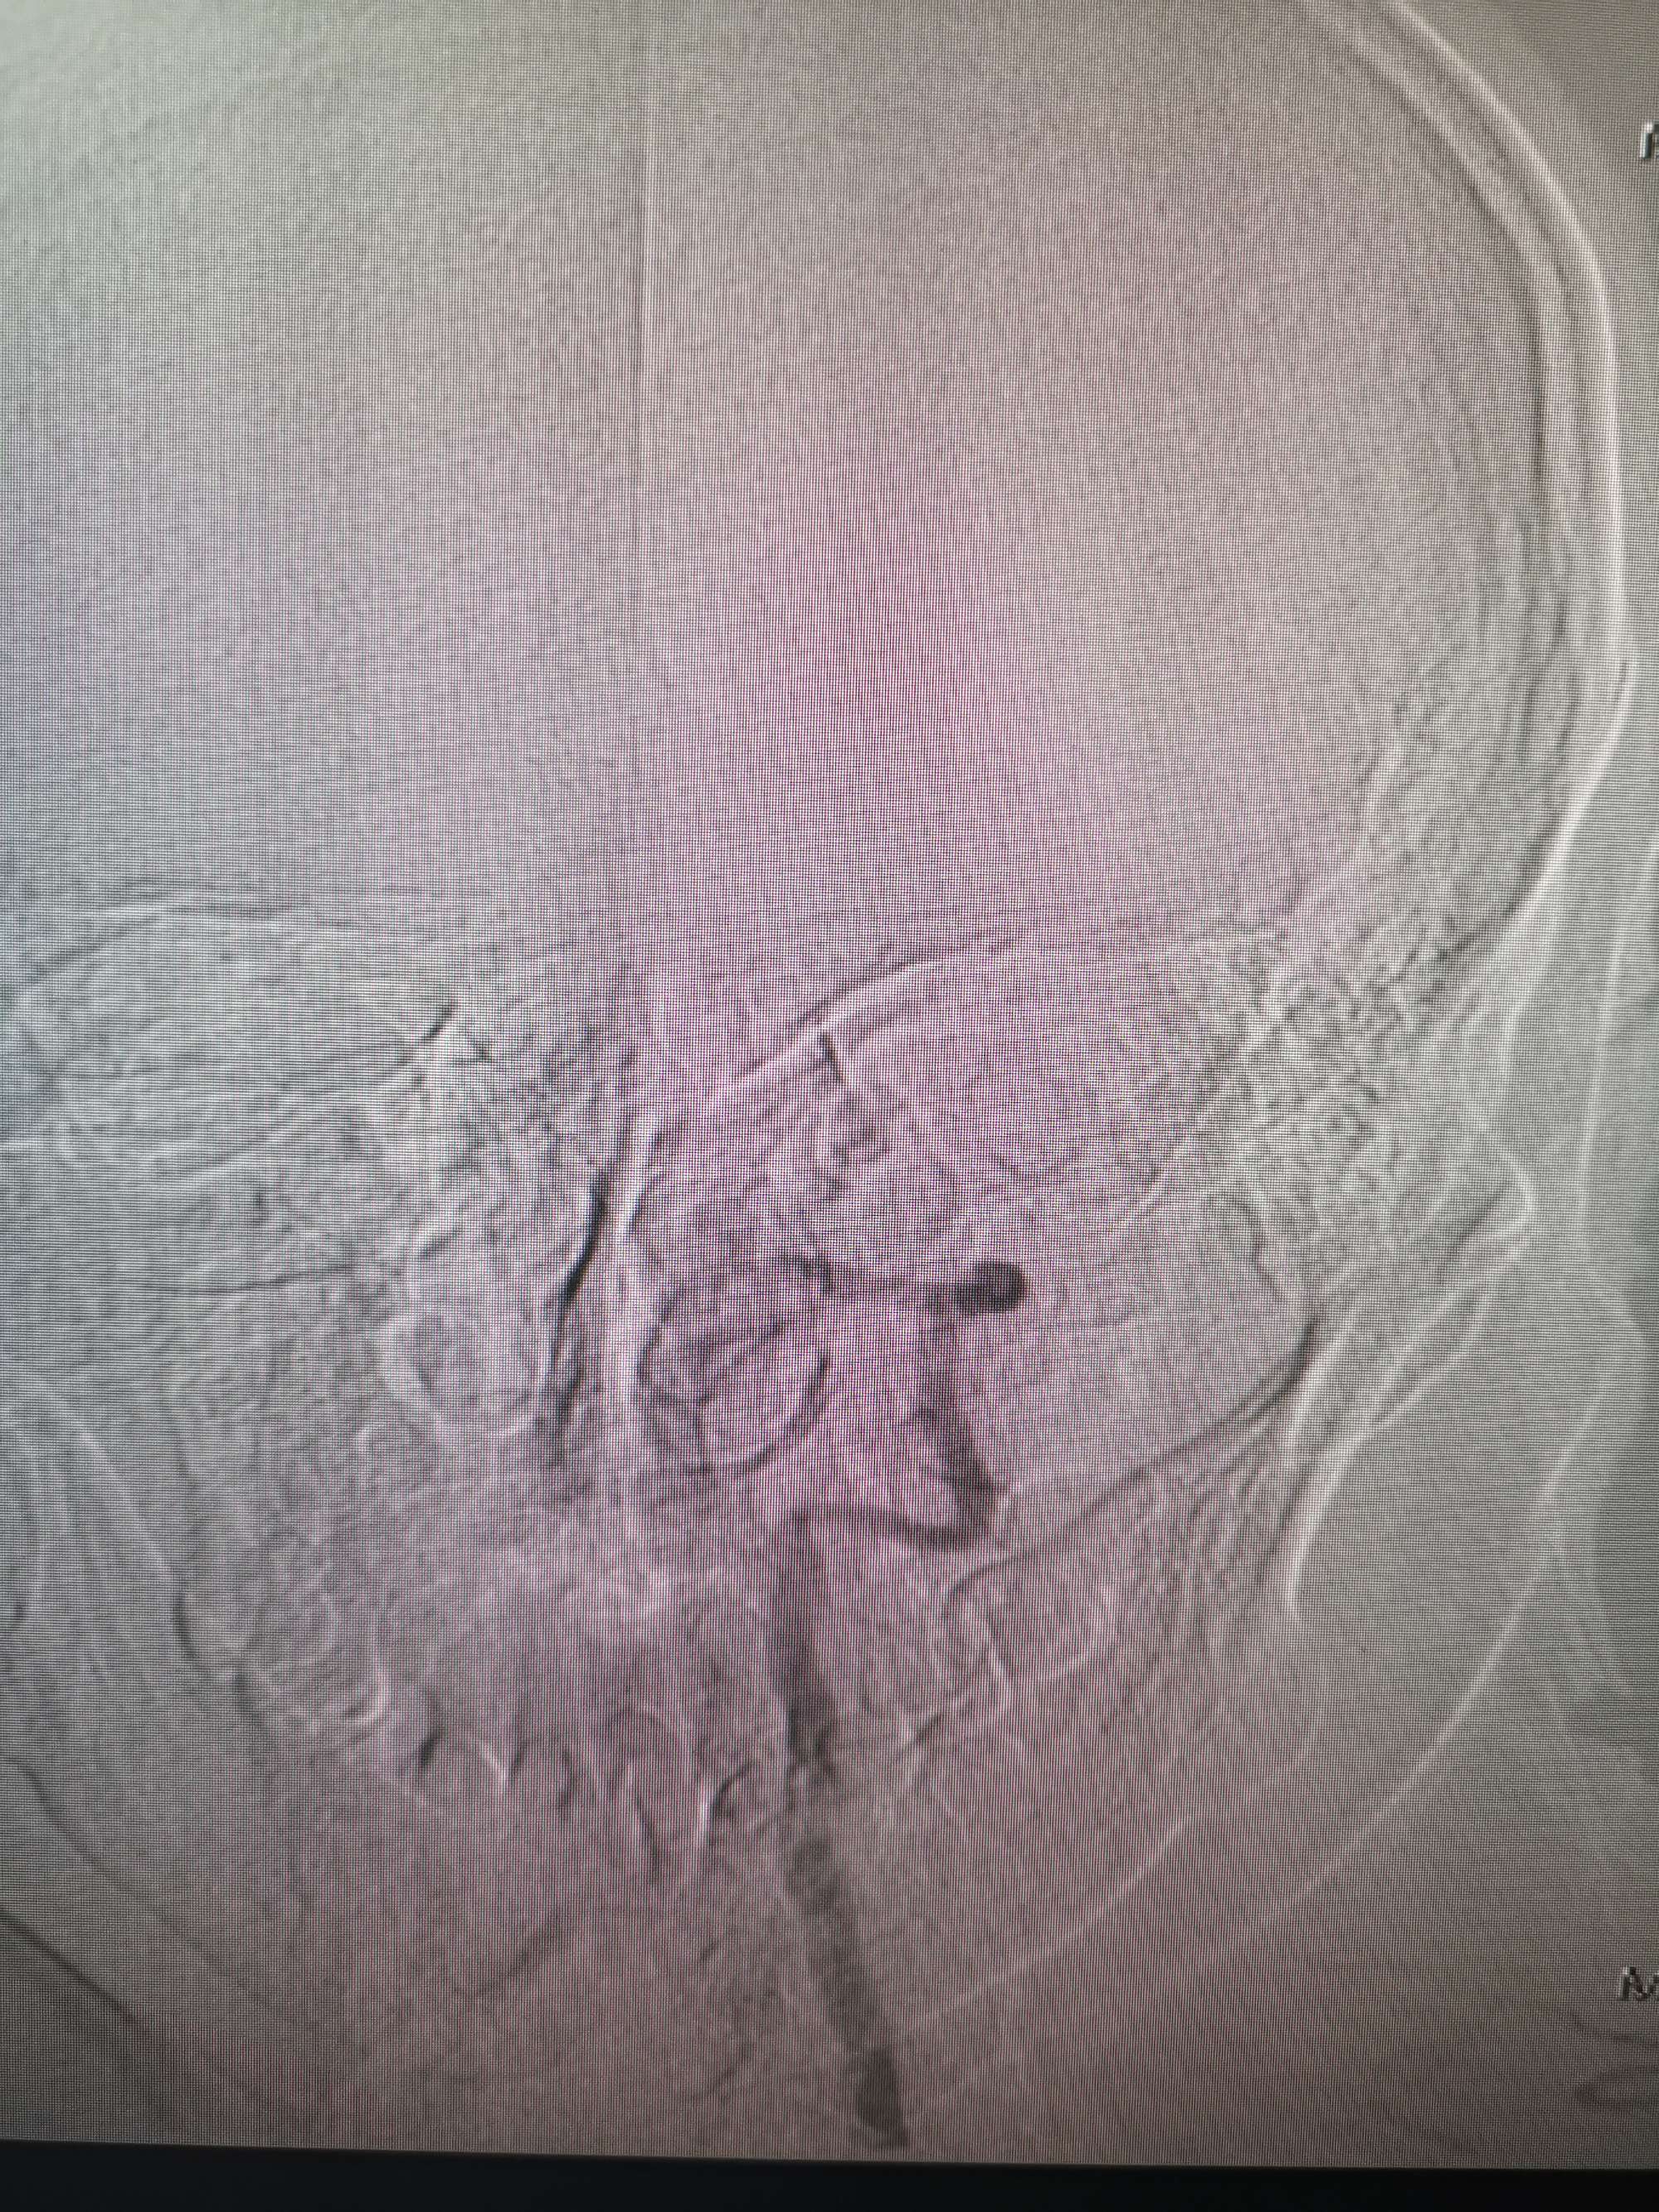

入院造影影像

术前再次造影评估